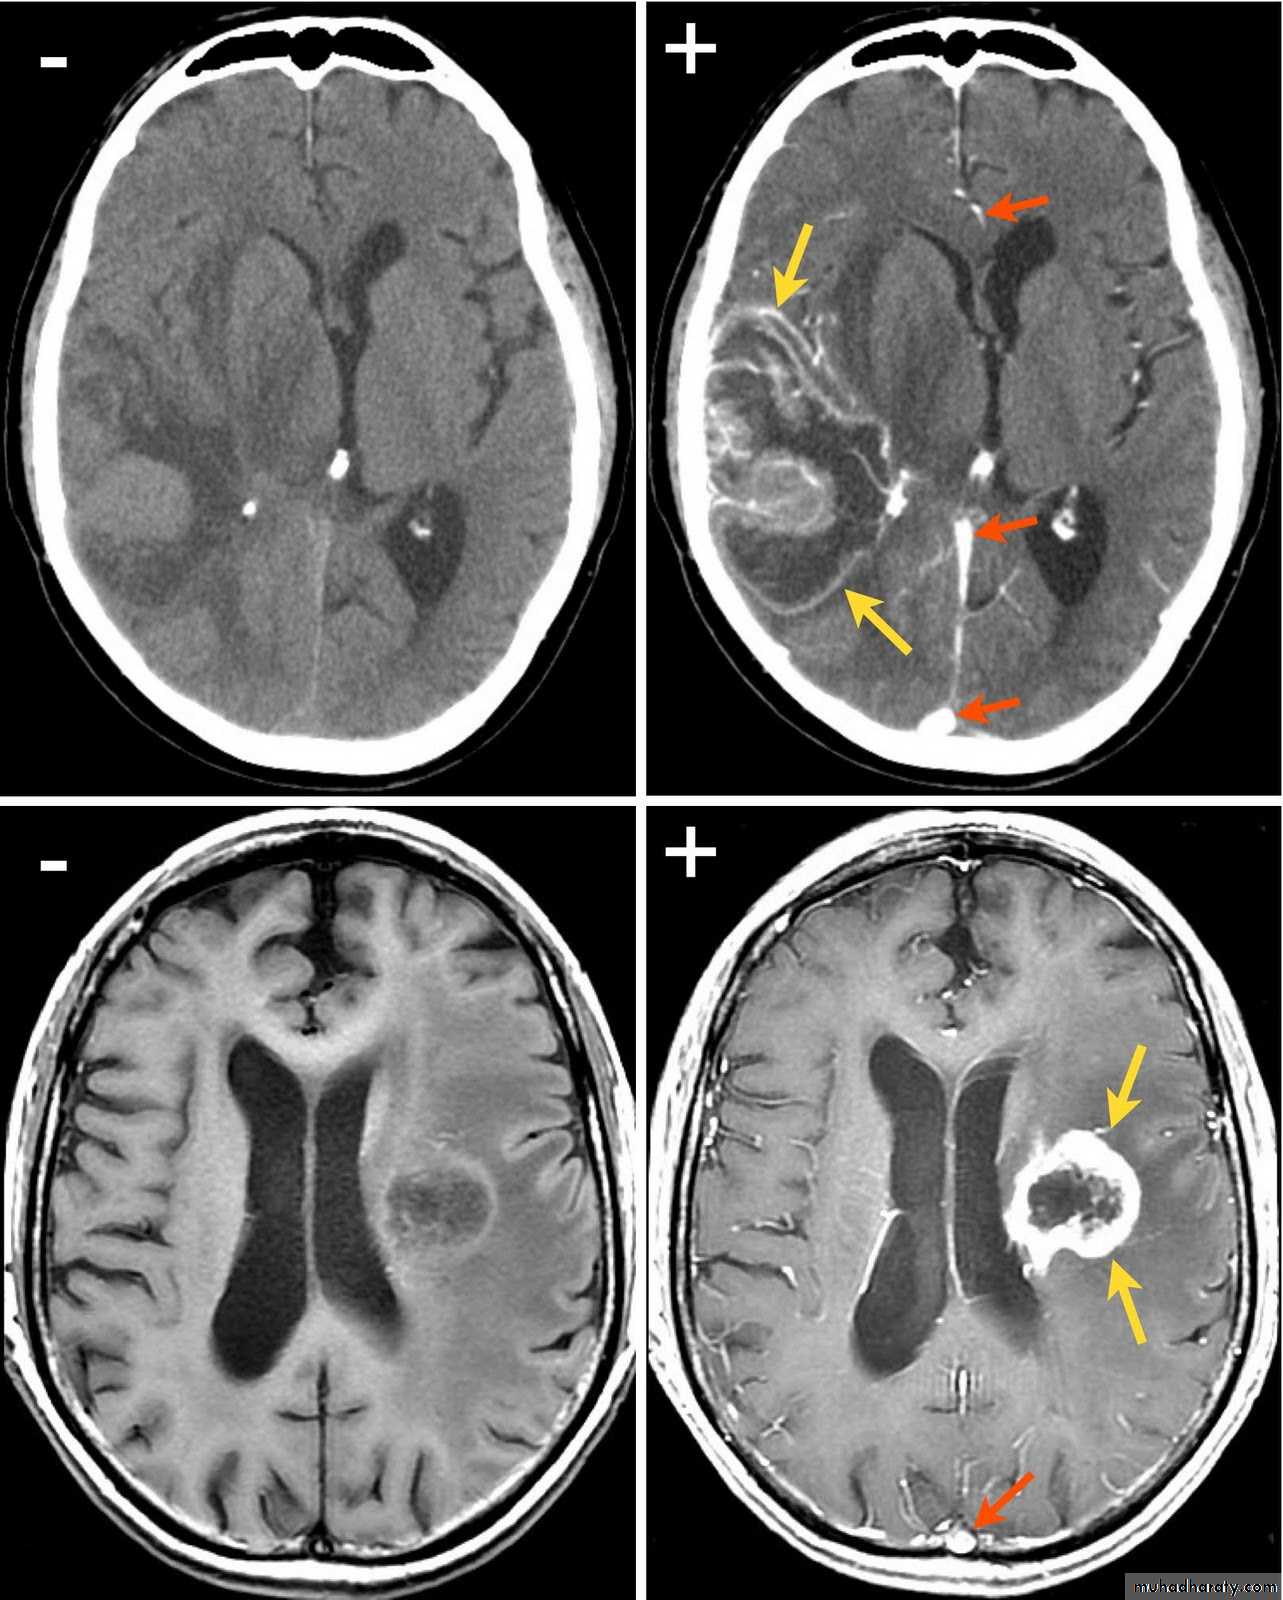

Secondary metastasis

Old age group above 50 Y , any lesion within the cerebellar hemisphere it is secondary metastasis unless proven otherwise F. from breast CA M. from bronchogenic CA .

Appear as nodular single or multiple lesion hypo dense or hyper dense .

Surrounded by per focal edema

Enhanced as solid or ring pattern of enhancement .

CT Scane